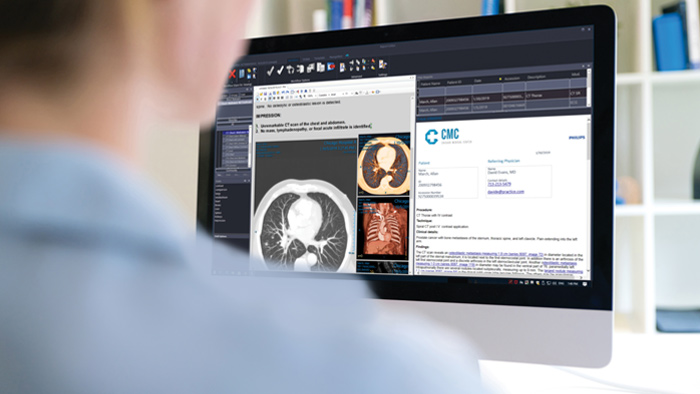

Let’s take a look at some of the immediate benefits of a unified approach. A single, unified workspace for radiology would incorporate advanced 3D post-processing and image distribution capabilities, opened in an additional viewer tab for ease.

A unified workspace would mean that users can easily launch the relevant analysis tools from among the 70+ advanced applications available across multiple clinical domains. Artificial Intelligence can play a role by automating tasks and workflows, predicting usage patterns.

An all-in-one workspace, fully integrated with the enterprise imaging platform and embedded in the diagnostic viewer, offers simple, efficient access to all needed tools across clinical domains. One-click access to advanced visualization tools – such as virtual colonoscopy, 3D processing, and spectral imaging – allows for efficient interpretation and supports diagnostic confidence.

Philips Diagnostic Radiology Viewer

Provides a single workspace with relevant tools for confident reading and insightful reporting, improving workflow and productivity by using embedded native 3D functionality and multimedia reporting.